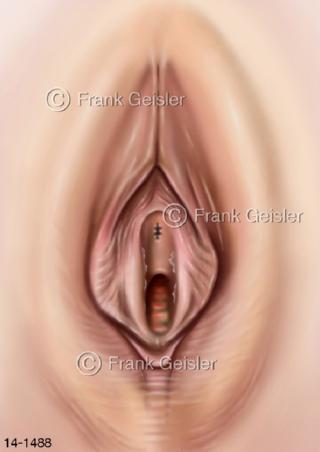

Bildergalerie Urogenitalsystem

Bilder zum Urogenitalsystem mit Urogenitalorgane, Urogenitaltrakt, zum Harn- und Geschlechtsapparat, Harnorgane und Geschlechtsorgane, Organe der Harnwege und der Fortpflanzung, Harnorgane und Geschlechtsorgane im männlichen und weiblichen Urogenitalsystem